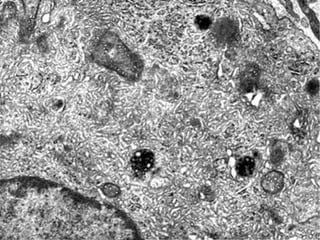

Este documento presenta imágenes microscópicas de diferentes tipos de tejidos y estructuras celulares teñidas con varios métodos histológicos. Incluye fotografías que muestran fibras de colágeno, elásticas y reticulares en diversos órganos, así como membranas basales y células especializadas de órganos como riñones, glándulas mamarias y próstata. El propósito es demostrar la aplicación de técnicas histológicas para visualizar componentes celulares y tej